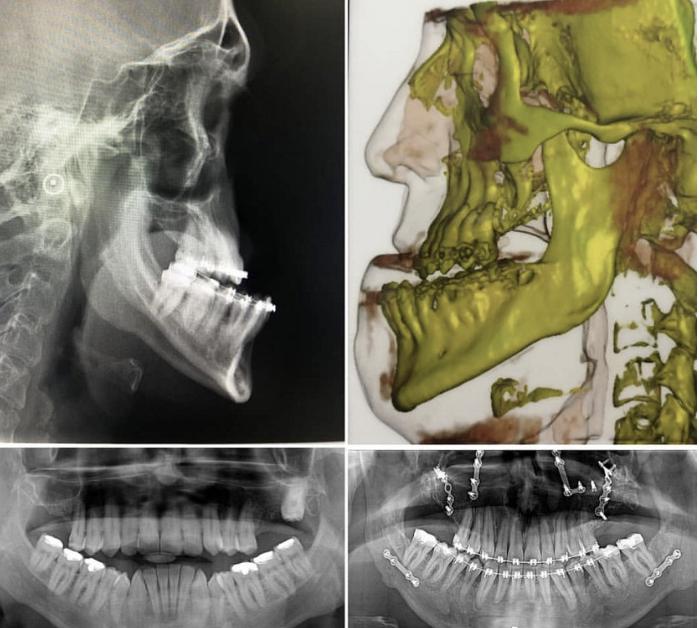

重度地包天案例,只能通过正颌手术矫正